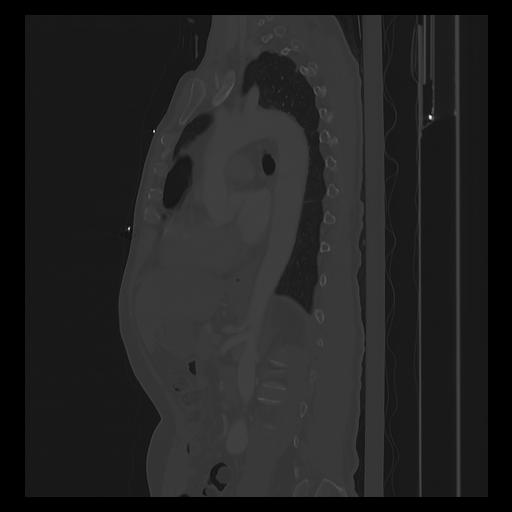

33 PULMON,CE,Sagittal,3.000,PULMON,Sagittal,